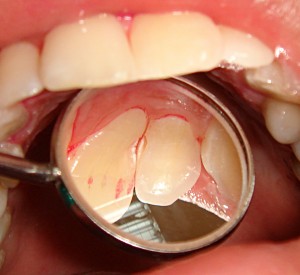

Средний кариес. Полостной дефект, достигающий эмалево-дентинного соединения и распространяющийся на слои дентина. Края полости обычно четкие, а ее стенки отвесные, плотные. Дно и стенки полости в различной степени пигментированные. Больной может жаловаться на застревание пищи, нередко жалоб не бывает. Зондирование дна и стенок такой полости безболезненно. Реакция на Холодовой раздражитель обычно не выражена.